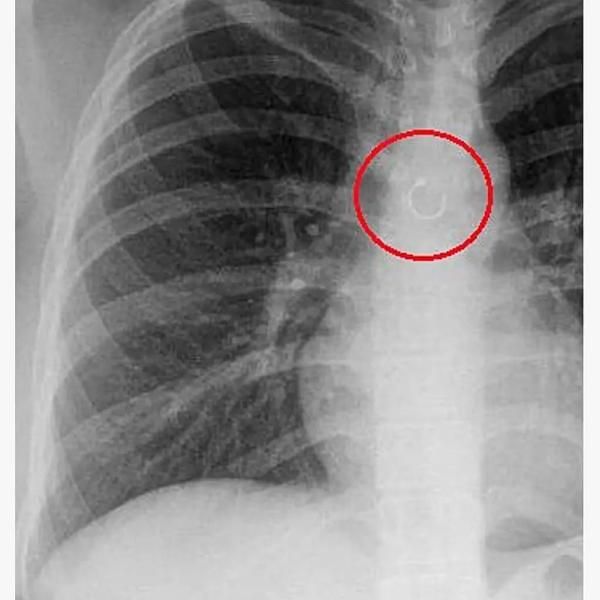

Жительница Мексики Моника Деянира Кабрера Барахас случайно вдохнула пирсинг из носа и проходила так несколько месяцев. Об этом пишет «Лента.ру».

26-летняя девушка рассказала, что внезапно стала страдать от постоянного кашля. Сначала она списала его на изменение погоды в ее родном штате Нуэво-Леон, но спустя месяц все же обратилась к врачу. Во время обследования в легком Барахас нашли металлическое кольцо — пирсинг из ее носа.

Барахас предположила, что однажды ночью шарик, удерживающий кольцо, раскрутился, и она вдохнула пирсинг во сне. На утро она, скорее всего, решила, что сняла его и куда-то положила, поэтому и не стала паниковать.

Пирсинг удалили из легкого девушки хирургическим путем. Врачам потребовалось две операции, чтобы добраться до него. Оказалось, что кольцо находилось в 0,5 миллиметра от аорты и могло пробить ее. Это было бы смертельно.